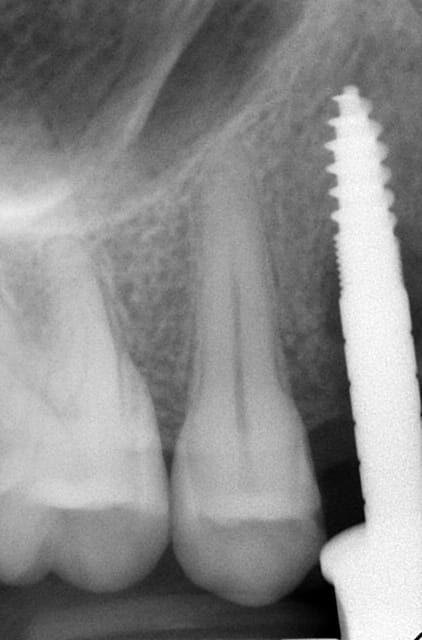

Un patient de 52 ans présente une fracture de racine au site 26.Après division de la racine, extraction de la dent,préparation de la cavité avec un foret conique triangulaire (3 faces,condensation de l´os), puis implantation à 50 Ncm (implant 10mm long, 4,5mm diamètre).Utilisation d´acide hyaluronique pour stimuler la synthèse des ostéoblastes.Pose d´un clip gingival pour préformer la gencive.Après 7 semaines, réalisation d´une empreinte fermée en 5 minutes.Une semaine après, fixation de la couronne définitive ( on observe déjà une ostéointégration).

Bonsoir merci pour ta question, comme tu vois sur la radioDVT il n y avait pas assez de place pour mettre un 6,5mm seulement la racine palatinale était d une longueur de 10/12 mm. Mon premier challenge etait d avoir une premiere stabilité supérieure à 40 Ncm.Le laboratoire est donc important pour que le patient puisse nettoyer facilement la région implantaire.

la radioDVT que j ai oublié de poster

L ossintegration est visible surtout en comparant avec la radio au moment de l implantation. Je cherche la photo pour la joindre.